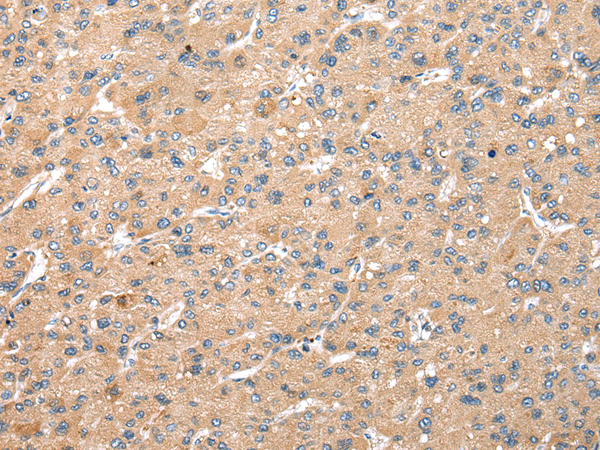

分类: 科研抗体货号: P02100别名:应用: WB,IHC反应种属: Human, Mouse